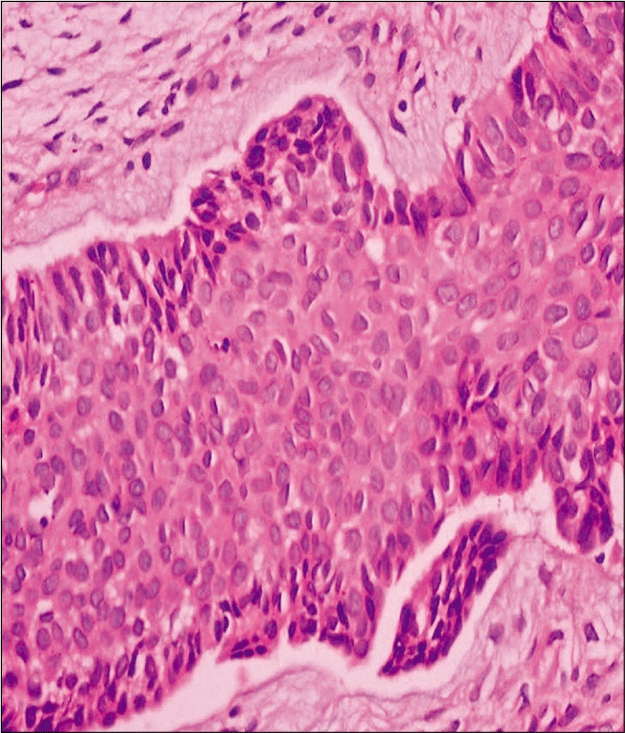

BASAL CELL CARCINOMA Pathology Made Simple Basal Cell Carcinoma Ncbi Basal cell carcinoma (bcc) is one of the most common malignant tumors worldwide, involving the skin. Basal cell carcinoma (bcc), previously known as basal cell epithelioma, is the most common cancer in humans. The second article in this. A) nodular basal cell carcinoma: Basal cell carcinoma is the most common skin cancer in the caucasian population. Basal cell carcinoma can. Basal Cell Carcinoma Ncbi.